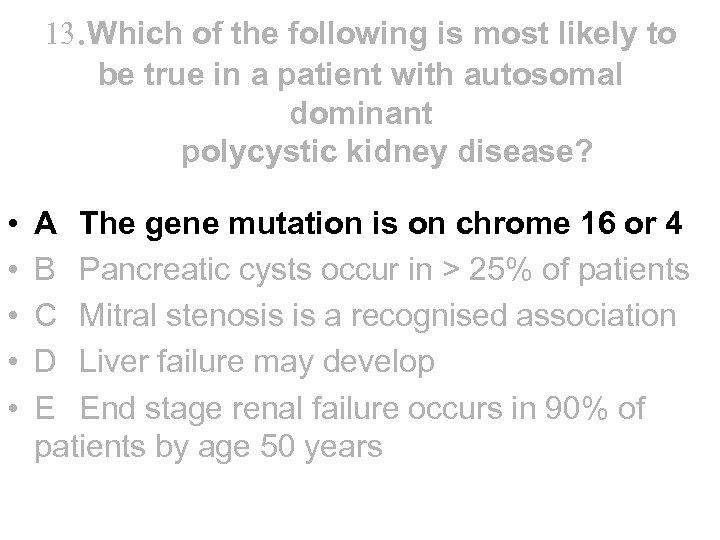

13. Which of the following is most likely to be true in a patient with autosomal dominant polycystic kidney disease? • A The gene mutation is on chrome 16 or 4 • B Pancreatic cysts occur in > 25% of patients • C Mitral stenosis is a recognised association • D Liver failure may develop • E End stage renal failure occurs in 90% of patients by age 50 years

13. Which of the following is most likely to be true in a patient with autosomal dominant polycystic kidney disease? • A The gene mutation is on chrome 16 or 4 • B Pancreatic cysts occur in > 25% of patients • C Mitral stenosis is a recognised association • D Liver failure may develop • E End stage renal failure occurs in 90% of patients by age 50 years

13. Which of the following is most likely to be true in a patient with autosomal dominant polycystic kidney disease? • • • A The gene mutation is on chrome 16 or 4 B Pancreatic cysts occur in > 25% of patients C Mitral stenosis is a recognised association D Liver failure may develop E End stage renal failure occurs in 90% of patients by age 50 years

13. Which of the following is most likely to be true in a patient with autosomal dominant polycystic kidney disease? • • • A The gene mutation is on chrome 16 or 4 B Pancreatic cysts occur in > 25% of patients C Mitral stenosis is a recognised association D Liver failure may develop E End stage renal failure occurs in 90% of patients by age 50 years

Polycystic kidneys • • • • Aetiology - PKD 1 gene on chrome 16 in 85%, PKD 2 gene on chrome 4 in 15% - Incidence is 1 in 1000 with “genetic anticipation” Presentation - often asymptomatic but also loin pain, haematuria, UTI, stones, HT or CRF Diagnosis - usually by ultrasound – but can’t definitely exclude till 30 years Extrarenal manifestations - liver cysts 40 -90% but liver failure rare, pancreatic cysts 5 -10% (not >25%) - berry aneurysms 3 -5%. Screening by MRA recommended if FH of SAH or has unexplained headache, but not routinely. Intervene if aneurysm >10 mm - MVP, AR (not Mitral Stenosis) and colonic diverticulae - erythrocytosis Treatment - tight control of BP may slow rate of decline of renal function Outcome - 50% PKD 1 and 2 develop ESRD by 55 and 70 years accounting for ~10% patients on RRT

Polycystic kidneys • • • • Aetiology - PKD 1 gene on chrome 16 in 85%, PKD 2 gene on chrome 4 in 15% - Incidence is 1 in 1000 with “genetic anticipation” Presentation - often asymptomatic but also loin pain, haematuria, UTI, stones, HT or CRF Diagnosis - usually by ultrasound – but can’t definitely exclude till 30 years Extrarenal manifestations - liver cysts 40 -90% but liver failure rare, pancreatic cysts 5 -10% (not >25%) - berry aneurysms 3 -5%. Screening by MRA recommended if FH of SAH or has unexplained headache, but not routinely. Intervene if aneurysm >10 mm - MVP, AR (not Mitral Stenosis) and colonic diverticulae - erythrocytosis Treatment - tight control of BP may slow rate of decline of renal function Outcome - 50% PKD 1 and 2 develop ESRD by 55 and 70 years accounting for ~10% patients on RRT